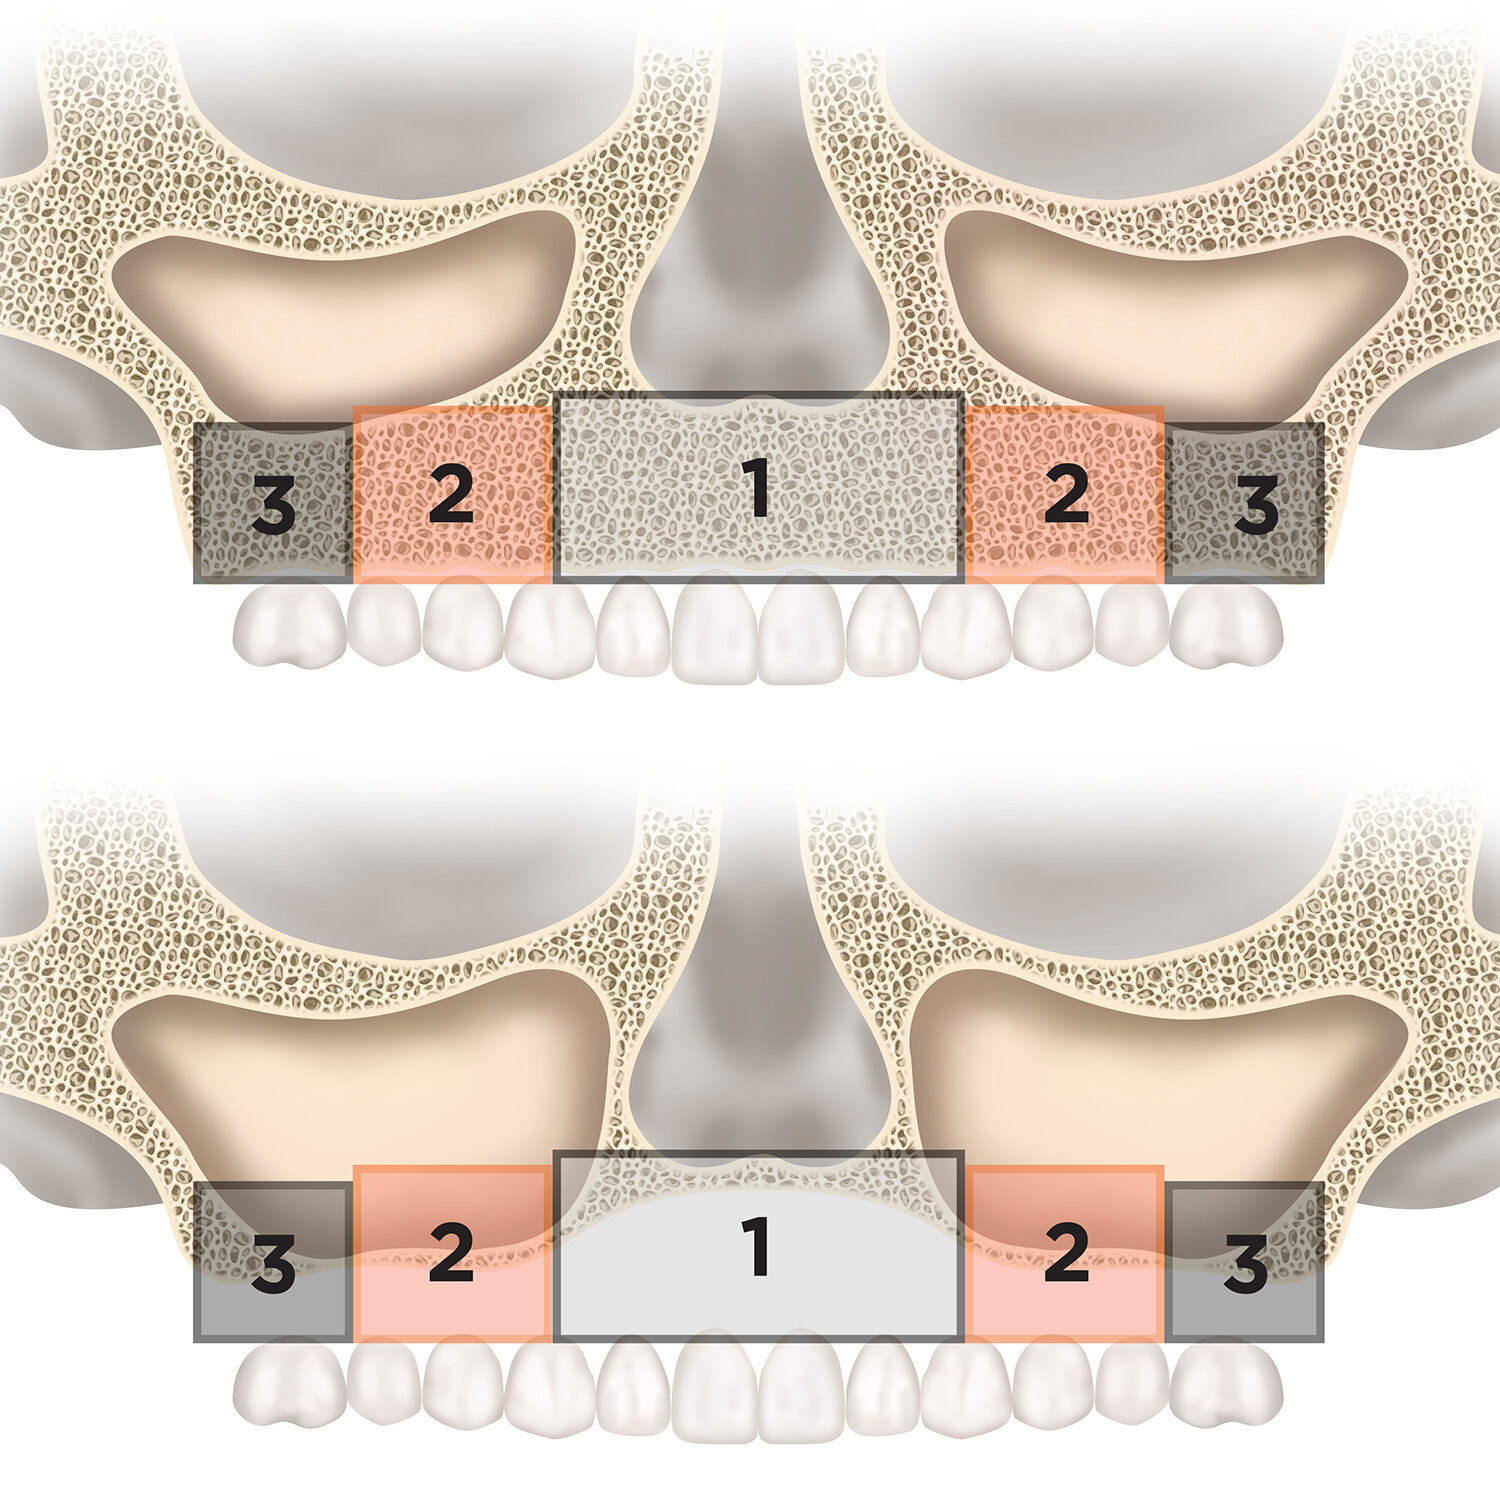

![Anterior maxilla showing resorption zones]()

Anterior maxilla showing resorption zones